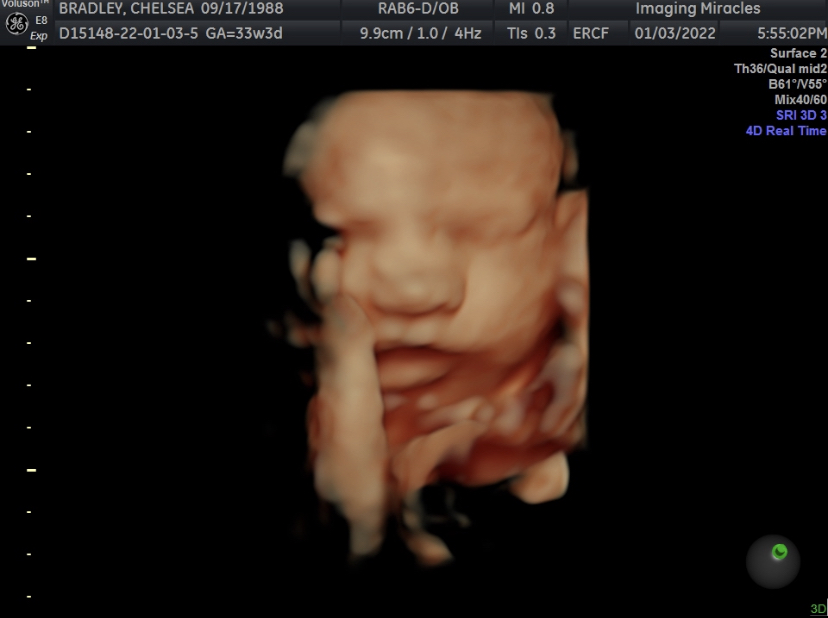

A fun craft + we’ve got a breech baby + 34 weeks!